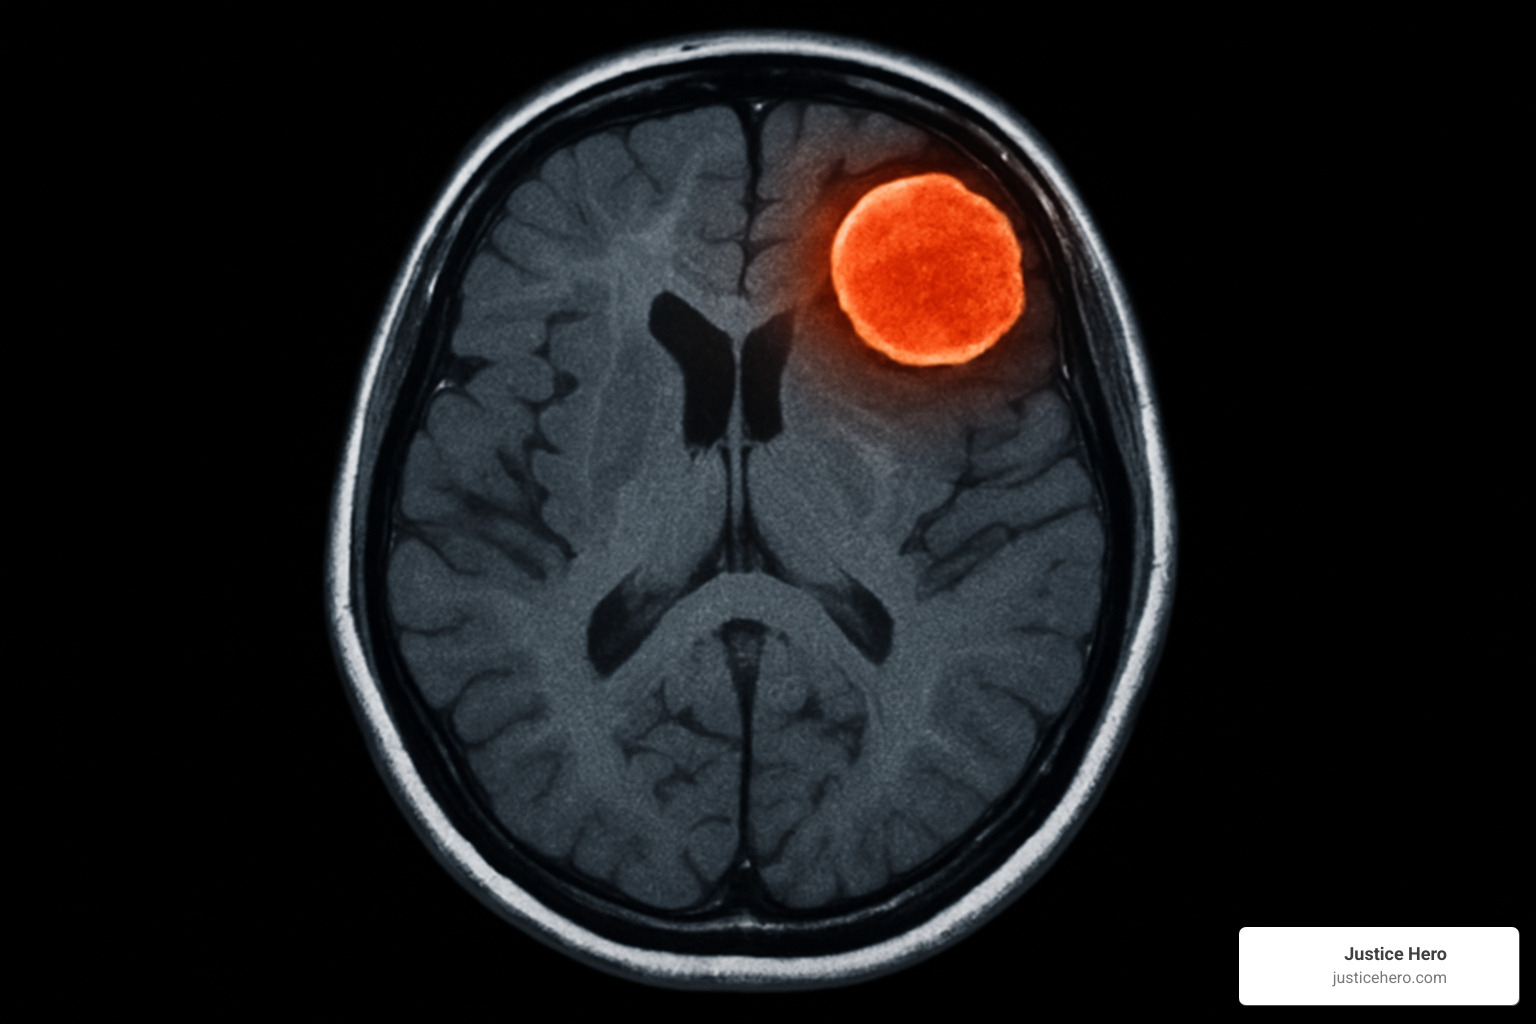

Meningiomas are tumors that grow in the meninges, which are like protective wrapping around your brain and spinal cord. While these tumors are usually not cancerous, they can cause serious problems when they get big enough to press against brain tissue. That's when doctors typically need to remove them surgically.

The game-changing evidence came from a major study published in The BMJ in March 2024. French researchers looked at data from over 108,000 women and made a startling find: women using medroxyprogesterone acetate (the hormone in Depo-Provera) had 5.55 times higher risk of developing brain tumors serious enough to require surgery.

What makes this even more concerning is that the research showed a clear pattern—the longer women used Depo-Provera, the higher their risk became. Women who used it for more than 12 months showed the biggest jump in risk.